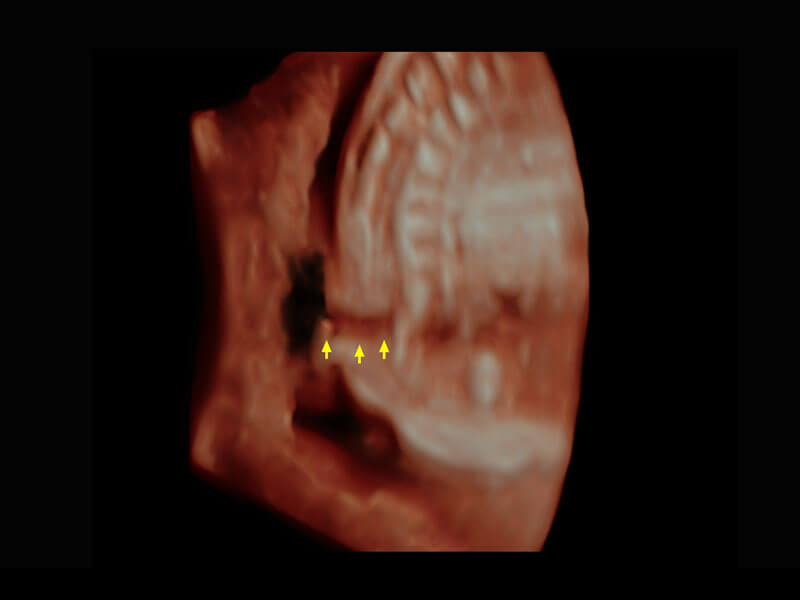

腔内妇科-宫腔分离

腔内妇科-卵巢

腔内三维-宫内节育器

腔内三维-光影成像